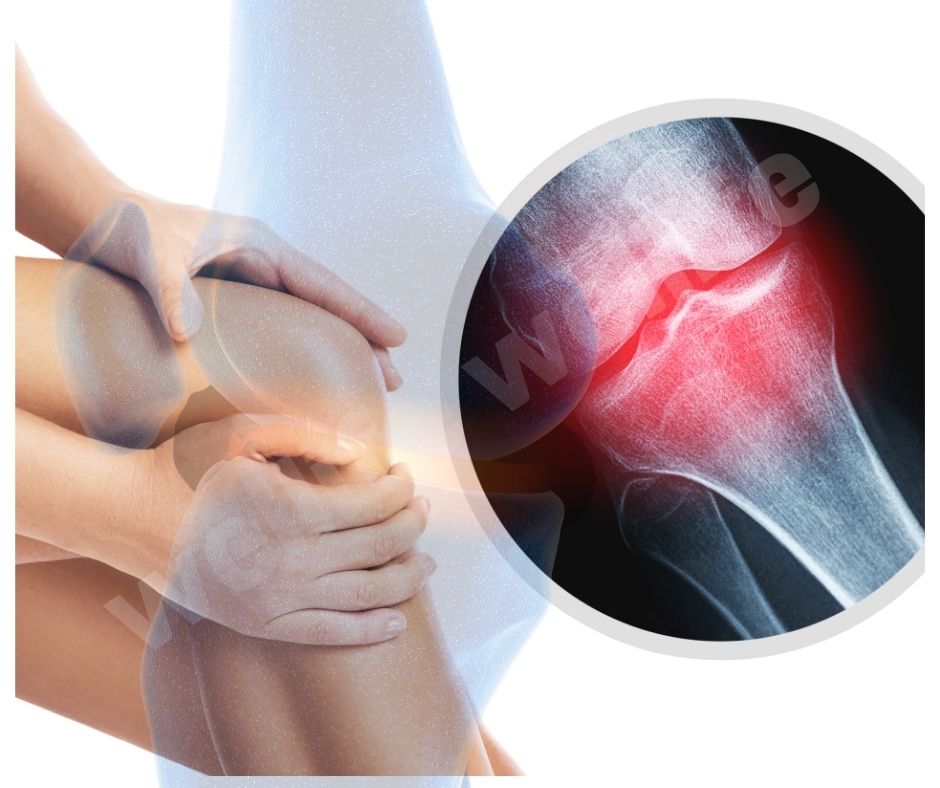

최근 연구에 따르면 글루코사민은 연골 세포의 생성을 촉진하고, 연골 조직의 회복을 돕는 효과가 있습니다. 2023년에 발표된 한 연구에서는 글루코사민이 연골 세포의 대사 활동을 증가시키고, 연골 조직의 손상을 줄이는 데 효과적이라는 결과를 보여주었습니다.

글루코사민의 효과 항염증 효과

글루코사민의 항염증 효과에 대한 연구도 활발히 진행되고 있습니다. 2022년에 발표된 한 연구에서는 글루코사민이 염증 매개체인 사이토카인의 생성을 억제하여 염증 반응을 줄이는 데 도움이 된다는 결과를 발표했습니다 (UVM College of Medicine). 이는 관절염 환자의 통증과 염증을 효과적으로 줄이는 데 중요한 역할을 합니다.